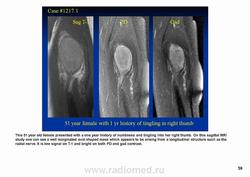

Диагноз неврилеммомы легко установить при расположении опухоли по ходу нерва, в других случаях необходимо гистологическое исследование.